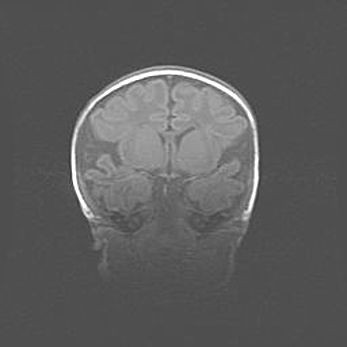

Наружная гидроцефалия с возможной атрофией височных областей.

Возраст: 28 дней

Вес: 3670 г

Пол: мужской

Окружность головы: 38 см

Срок гестации: 40 недель

Гидроцефалия головного мозга у новорожденных – это заболевание, которое характеризуется скоплением избыточного количества спинномозговой жидкости в желудочковой системе головного мозга в результате затруднения её перемещения от места выработки к месту поглощения в кровеносную систему или вследствие нарушения абсорбции. При открытой наружной форме гидроцефалии у новорожденных расширяются и переполняются субарахноидные пространства.

При нормотензивных  формах,  которые,  как  правило,  являются  следствием  перенесенных ишемических  повреждений  паренхимы  мозга,  возможно  сочетание микроцефалии  с нормотензивной гидроцефалией. В основе данных изменений лежит атрофия больших полушарий с преимущественной  локализацией  в  лобно-височных  областях.